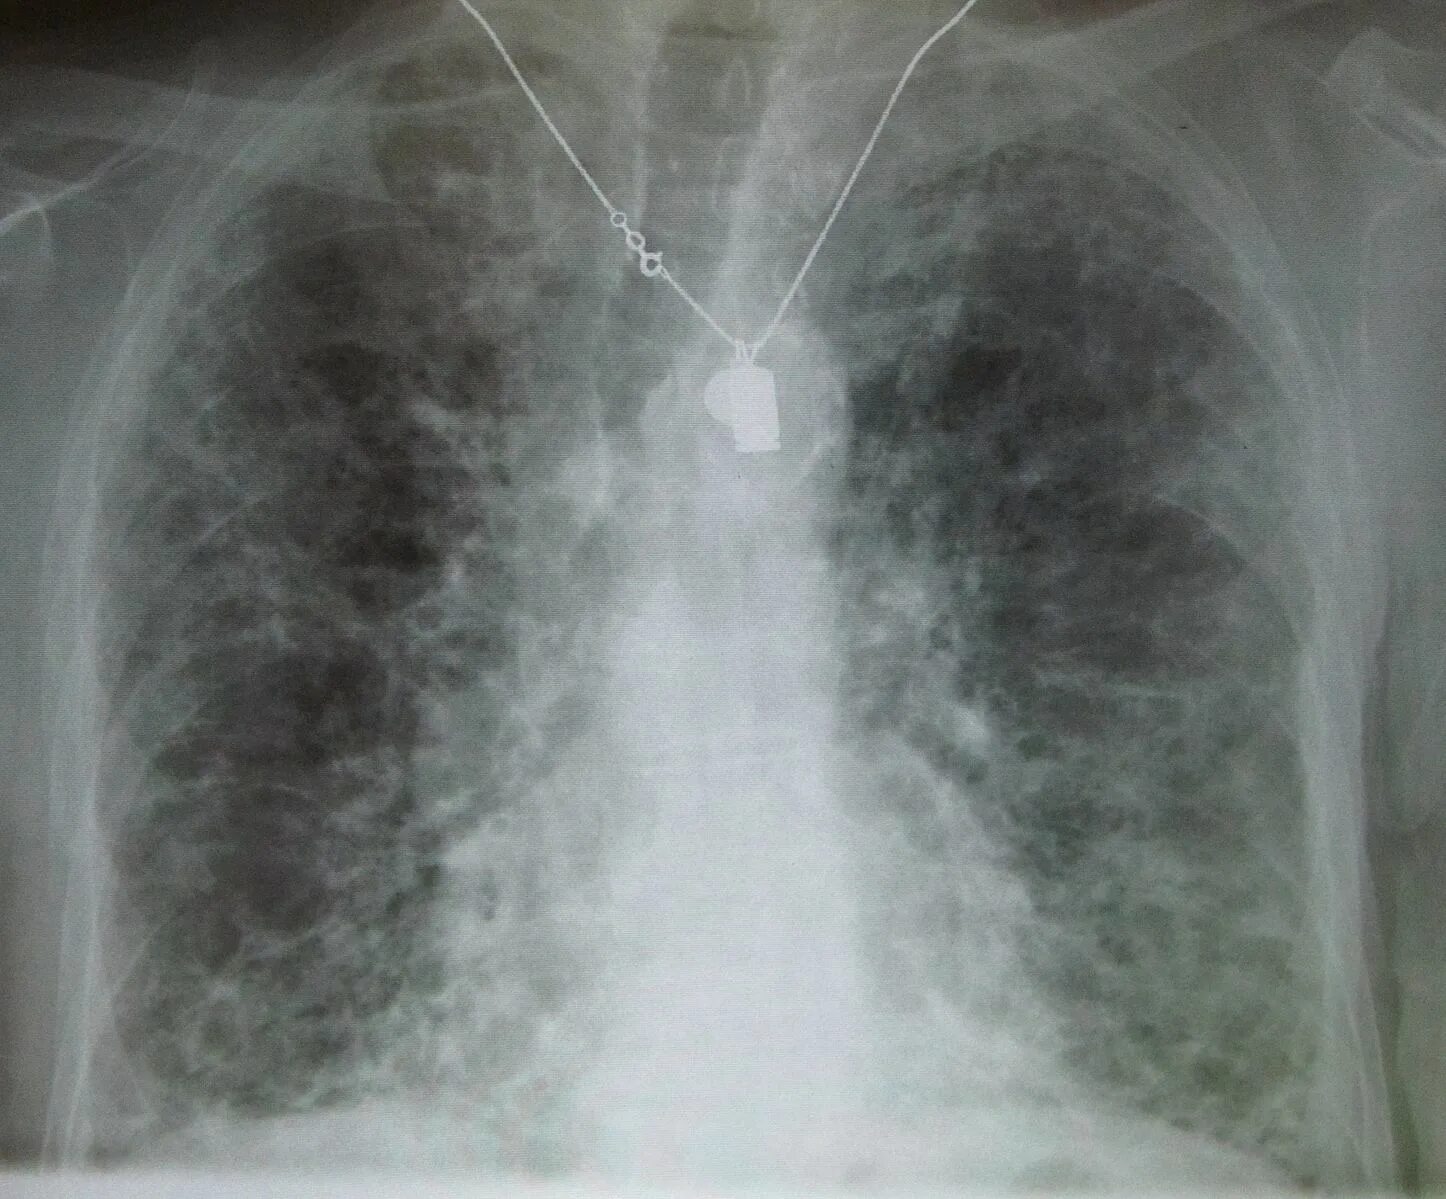

Пневмофиброзные изменения